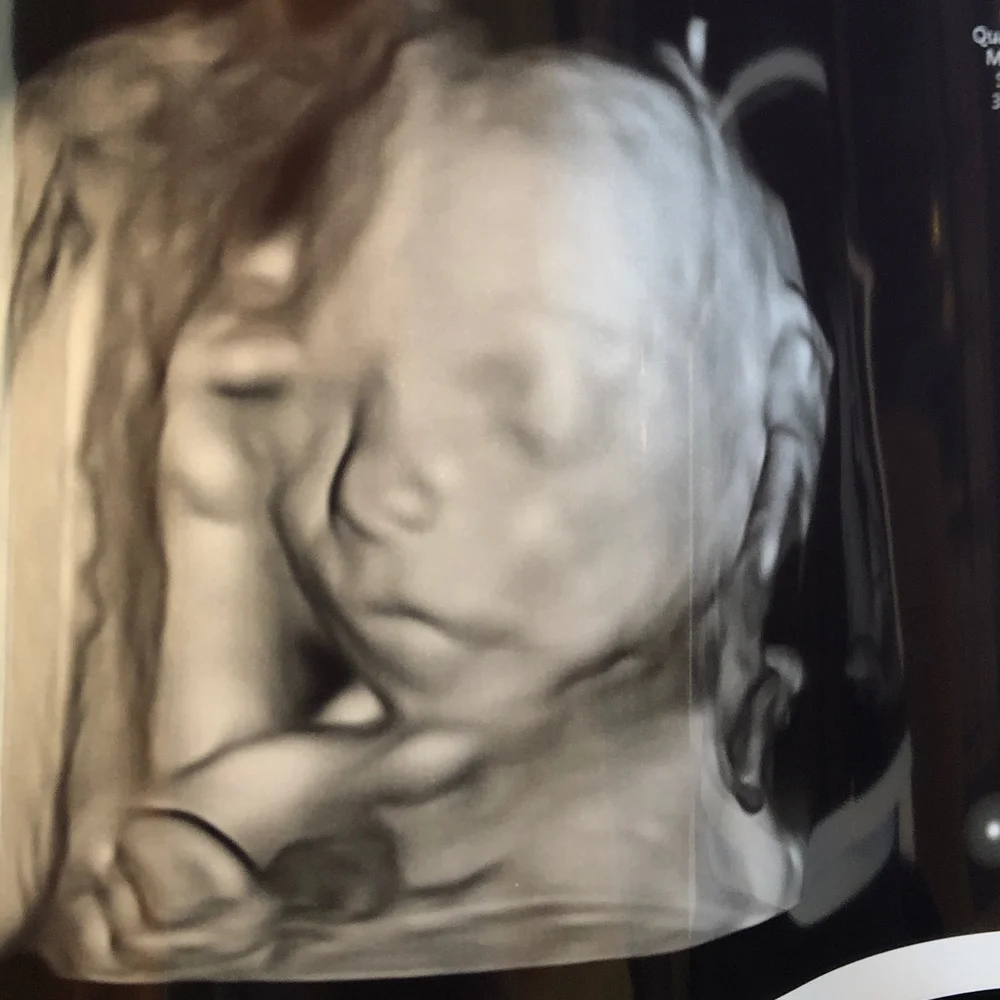

hair on ultrasound 20 weeks

On an ultrasound We went for the last growth scan last night. Hair is supposed to look whispy.

Hair on ultrasound 20 weeks Sunday July 17 2022 Edit. Why do you need a full bladder for 20 week ultrasound. The hair color of your baby cannot be determined or known on an ultrasound at this time.

Around 20 weeks fine downy hair starts to sprout from these follicles on the eyebrows upper lip and chin. Can you see hair on a 2D. I was so surprised that we could see it on a regular ultrasound.

The US tech is getting her head measurement and she said shes got a lot of hair already. I guess at the later ones there. All Curled Up At 18 Weeks Old Loveatfirstsight Baby Ultrasound Ultrasound 4d Ultrasound Pictures 4d Ultrasound.

Yes - I could see little spikes of hair on the babys head at a 32 week growth check. Do they check cervix at 20 week scan. Around 20 weeks fine downy hair starts to sprout from these follicles on the eyebrows upper.

Just had our 32 week growth scan and apparently baby girl has a tiny little tuft of hair at the back of her head. Apr 4 2020 at 125 AM.